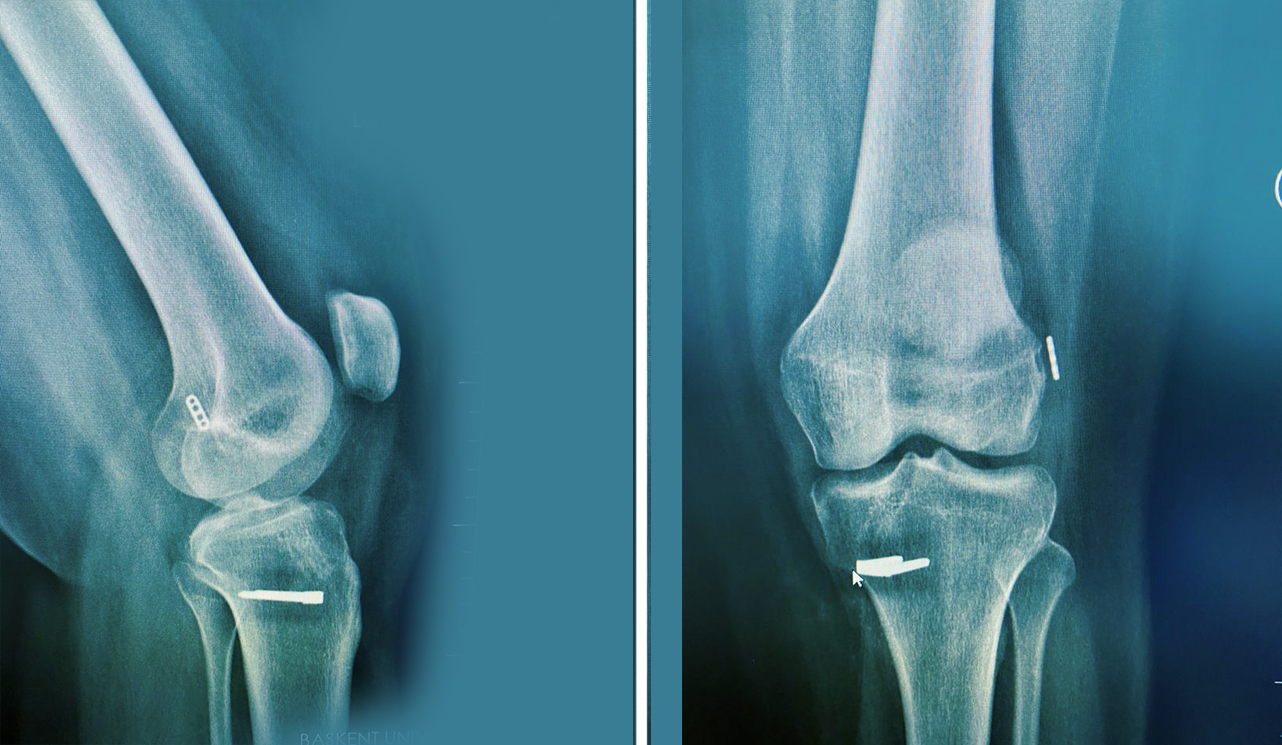

Vücudun çok sayıdaki dokusu özellikle de kas ve tendonlar koşu esnasında ciddi olarak etkilenir. Hemen bütün kas gruplarının aktivitesi artar. EMG çalışmaları kuadriseps kasında % 172, hemstringlerde % 86, tibialis anterior kasında % 56 ve triseps ka sında ise % 95 oranında aktivite artışı göstermektedir.

Koşucularda problem alt ekstremitelere art arda binen yüklerden kaynaklanır. Her adımda vücut ağırlığının 1,5-5 misli yük ayaklara etki etmektedir. Koşan bir erişkinde her 1500 metrede, her bir ayağa 150-200 tonluk bir ağırlık binmektedir. Bütün bu yüklenmeler sonucu dokularda patolojik değişikliklerin ortaya çıkması mümkün olmaktadır